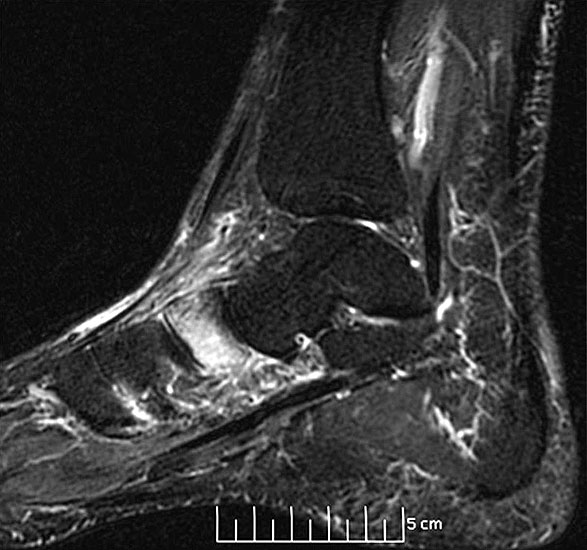

Diagnostische Methode der Wahl ist das MRT, das eine sichere Diagnosestellung erlaubt. Dabei kommt es  im betroffenen Knochen zur signalarmen Darstellung in der T1-Wichtung während T2 gewichtete Darstellungen als Folge des Ödems mit einer  Signalanreicherung in den betroffenen Skelettabschnitten und oft auch in den benachbarten Weichteilen imponieren

10.

Beim TKMÖ ist in der Regel nach ca. 6-10 Monaten ab Einsetzen der ersten Symptome mit einer vollständigen Restitutio (Abb. 8 und 9) ist zu rechnen {ref: 21733459, 15045549, 15767100, 20640992, 18353586, 15049532}

Am besten eignet sich zur Verlaufskontrolle das MRT 15, Kontrollen in kürzeren als 3 monatigen Abständen, machen es aber meist schwierig eine Änderung in der Bildgebung zu erkennen.